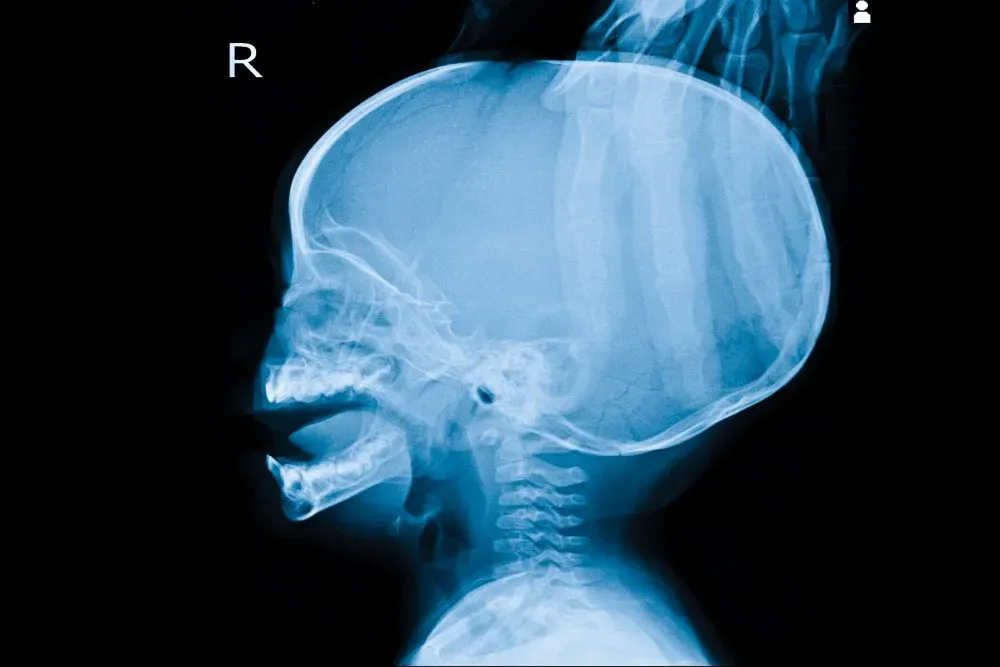

Hydrocephalus is when too much cerebrospinal fluid (CSF) builds up in the brain's ventricles.

When you have hydrocephalus, the clear fluid builds up in cavities called ventricles in your brain, eventually placing pressure on sensitive brain tissues. Unchecked hydrocephalus can cause brain damage and even death.